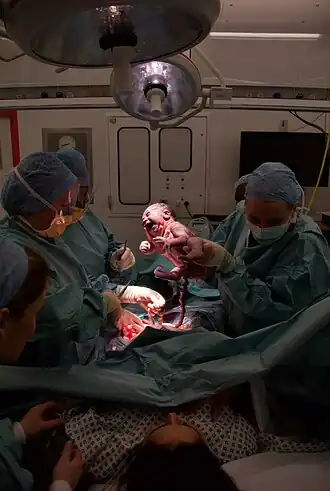

| Momento em que o bebé é retirado do útero durante uma cesariana | |

Um parto por cesariana tem geralmente a duração de 45 minutos a uma hora.[1] Pode ser realizado sob anestesia espinhal, em que a mulher se encontra consciente, ou sob anestesia geral.[1] É introduzido um catéter urinário para drenar a bexiga e o abdómen é limpo com um antisséptico.[1] Geralmente é feita uma incisão com cerca de 15 cm no abdómen inferior da mulher.[1] O útero é depois aberto com uma segunda incisão e o bebé retirado.[1] No fim, as incisões são suturadas.[1] Geralmente a mulher pode dar início à amamentação assim que desperta da anestesia e sai da sala de operações.[4] Na maior parte dos casos, as cesarianas requerem alguns dias de internamento hospitalar até a mulher ter alta.[1]